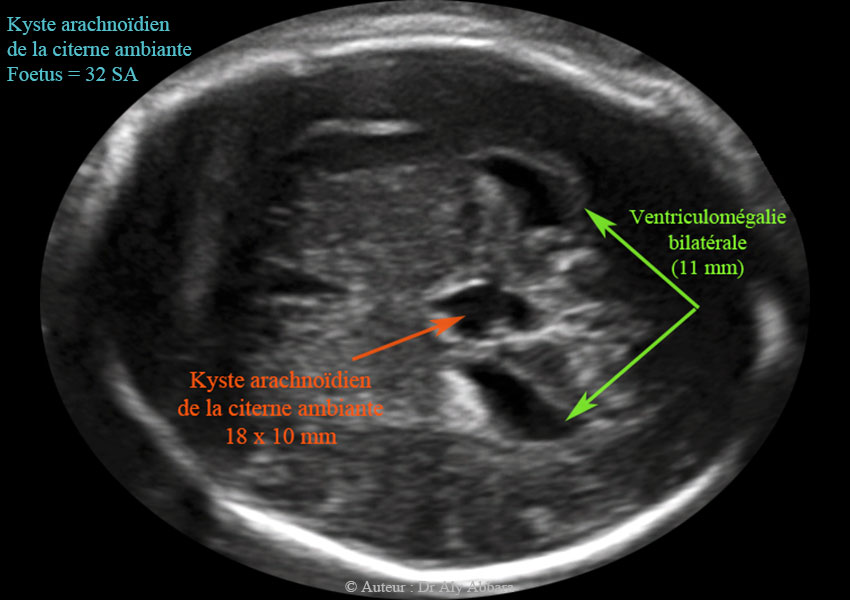

Images échographiques animées montrant la présence d'un probable kyste arachnoïdien cérébral (ou neuroépithélial) évoluant dans la citerne ambiante (en arrière du corps calleux) et mesurant 11 x 18 x 9 mm et associé à une ventriculomégalie bilatérale se caractérisant par l'élargissement des deux carrefours ventriculaires postérieurs qui mesurent 11 - 12 mm de largeur.

Le 3e et le 4e ventricules ne sont pas dilatés.

Il s'agit d'une anomalie isolée chez un foetus de 32 SA; aux échographies du 2e trimestre ce kyste n'était présent.